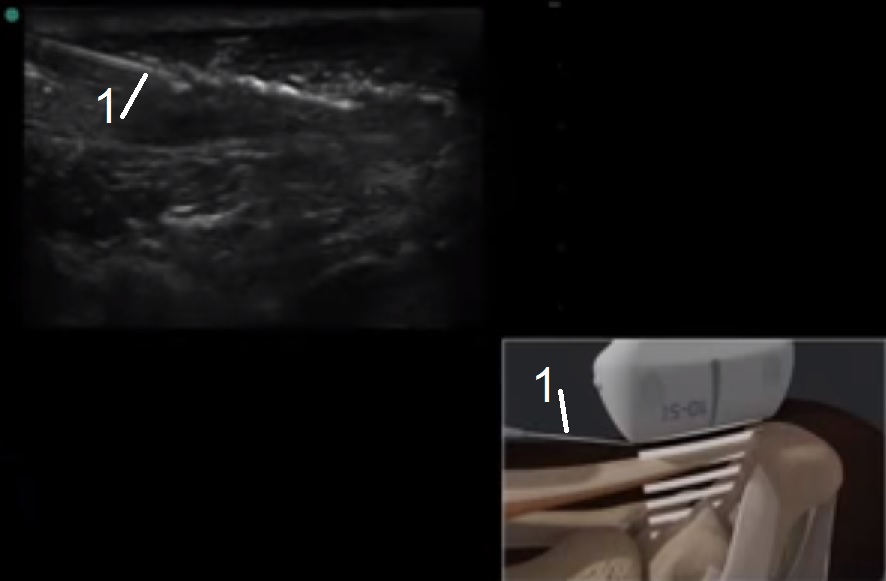

Bild: Fuß und Sprunggelenk, Achillessehne, Injektion

Nadel